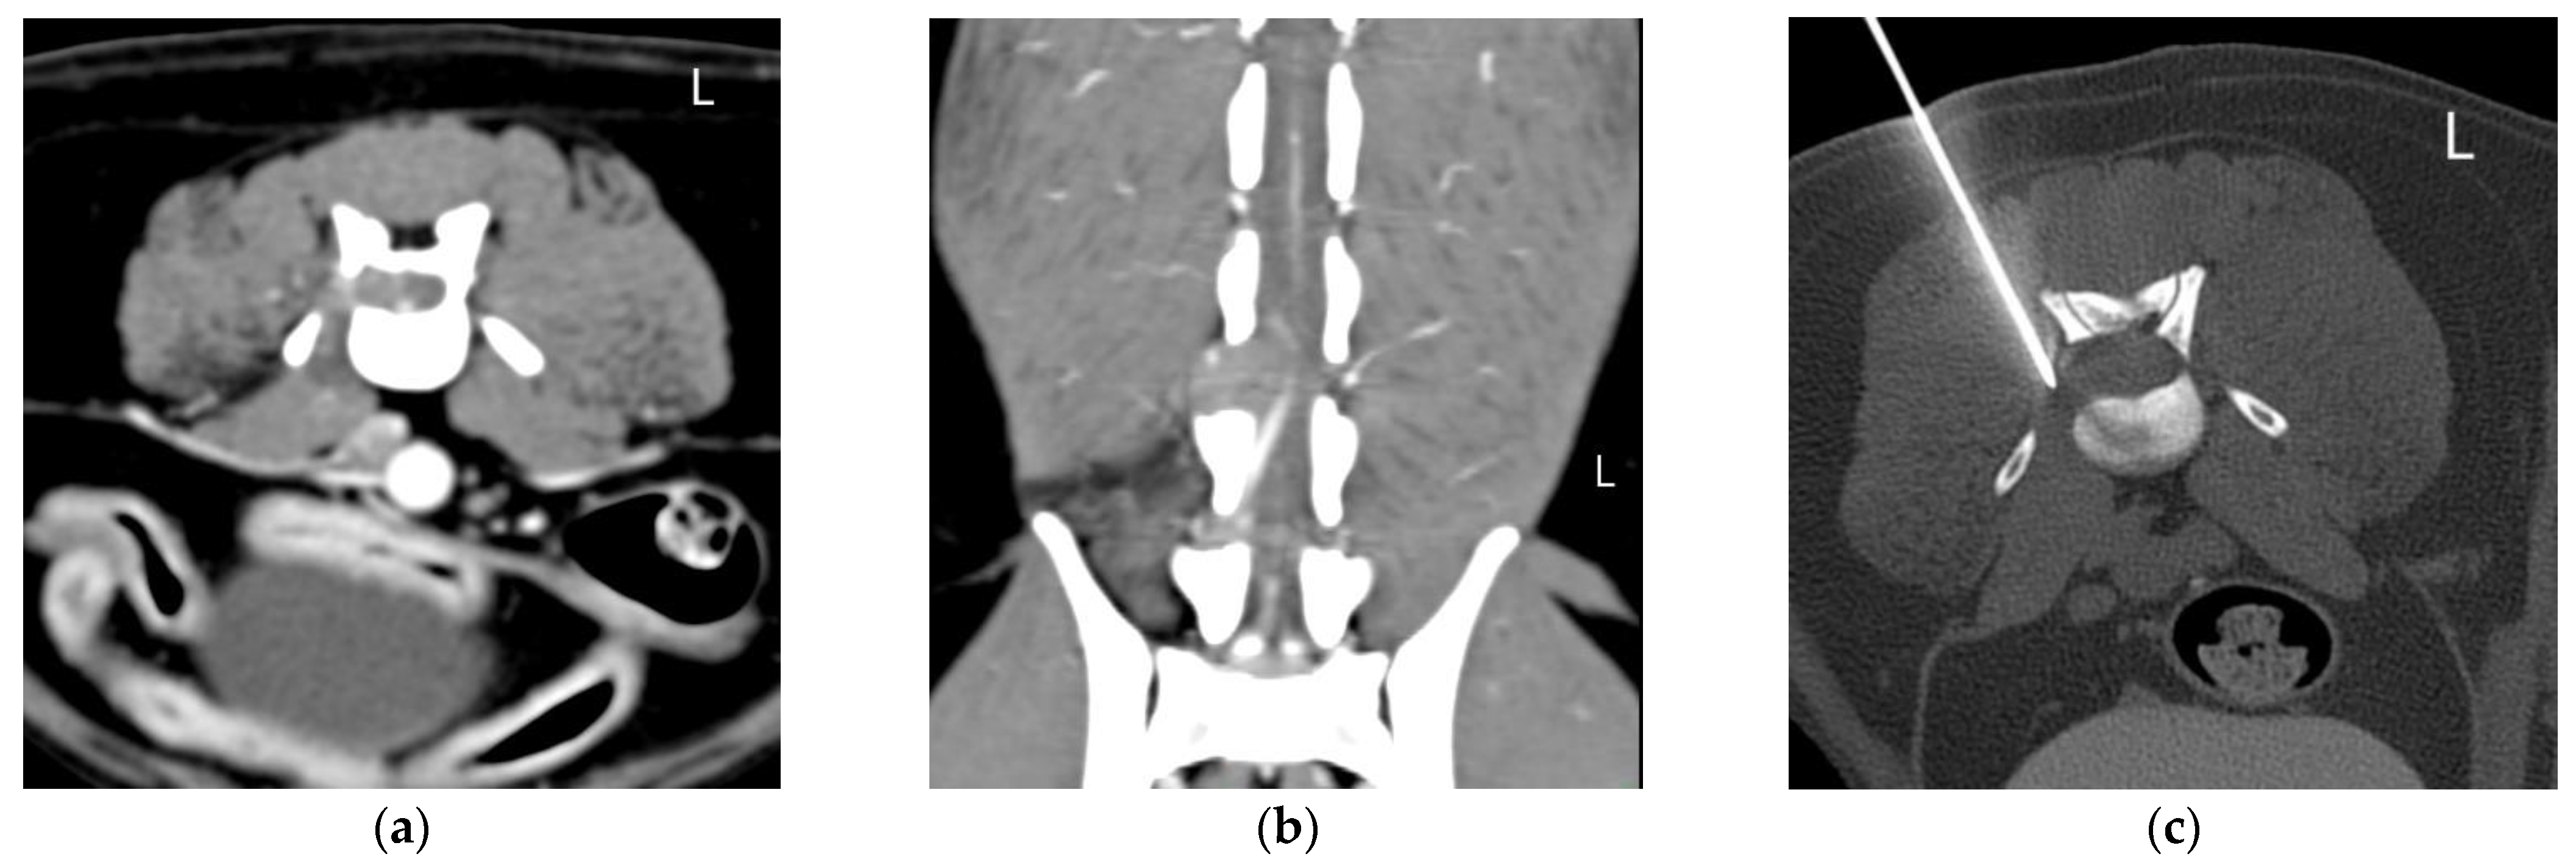

2.2. Equipment and Technique

| 4 | Ferret Female neutered 6 yo | Acute onset of paraplegia | NE: Absence of PR and nociception and decreased withdrawal reflex in both HLs. CTMR cut off L3. TL hyperesthesia. NLoc: T3-L3 myelopathy and associated spinal shock | Polyostotic aggressive bone lesions (mainly lytic) in vertebrae and ribs, worst on L1. Non-primary bone tumor | Right L1 VB and TP | Lymphoma | Disseminated lymphoma (necropsy) |

| 5 | Canine Labrador retriever Male intact 2 yo | Chronic progressive HLs weakness and ataxia. | NE: ambulatory paraparesis and proprioceptive ataxia of the HLs. Paresis of the tail. Decreased muscle tone of HLs and tail. Absent PR and SR in the HLs and decreased perineal reflex. NLoc: L4-Cd5 myelopathy +/− L4-Cd5 nerve roots +/− L4-Cd5 spinal nerves | Severe thickening/mass located in the epidural space in the vertebral canal along L5–L7, expanding to the L5–L6 IVF (R > L). Infiltrative neoplasia (lymphoma, sarcoma) | Right L5–L6 IVF | Lymphoma | |